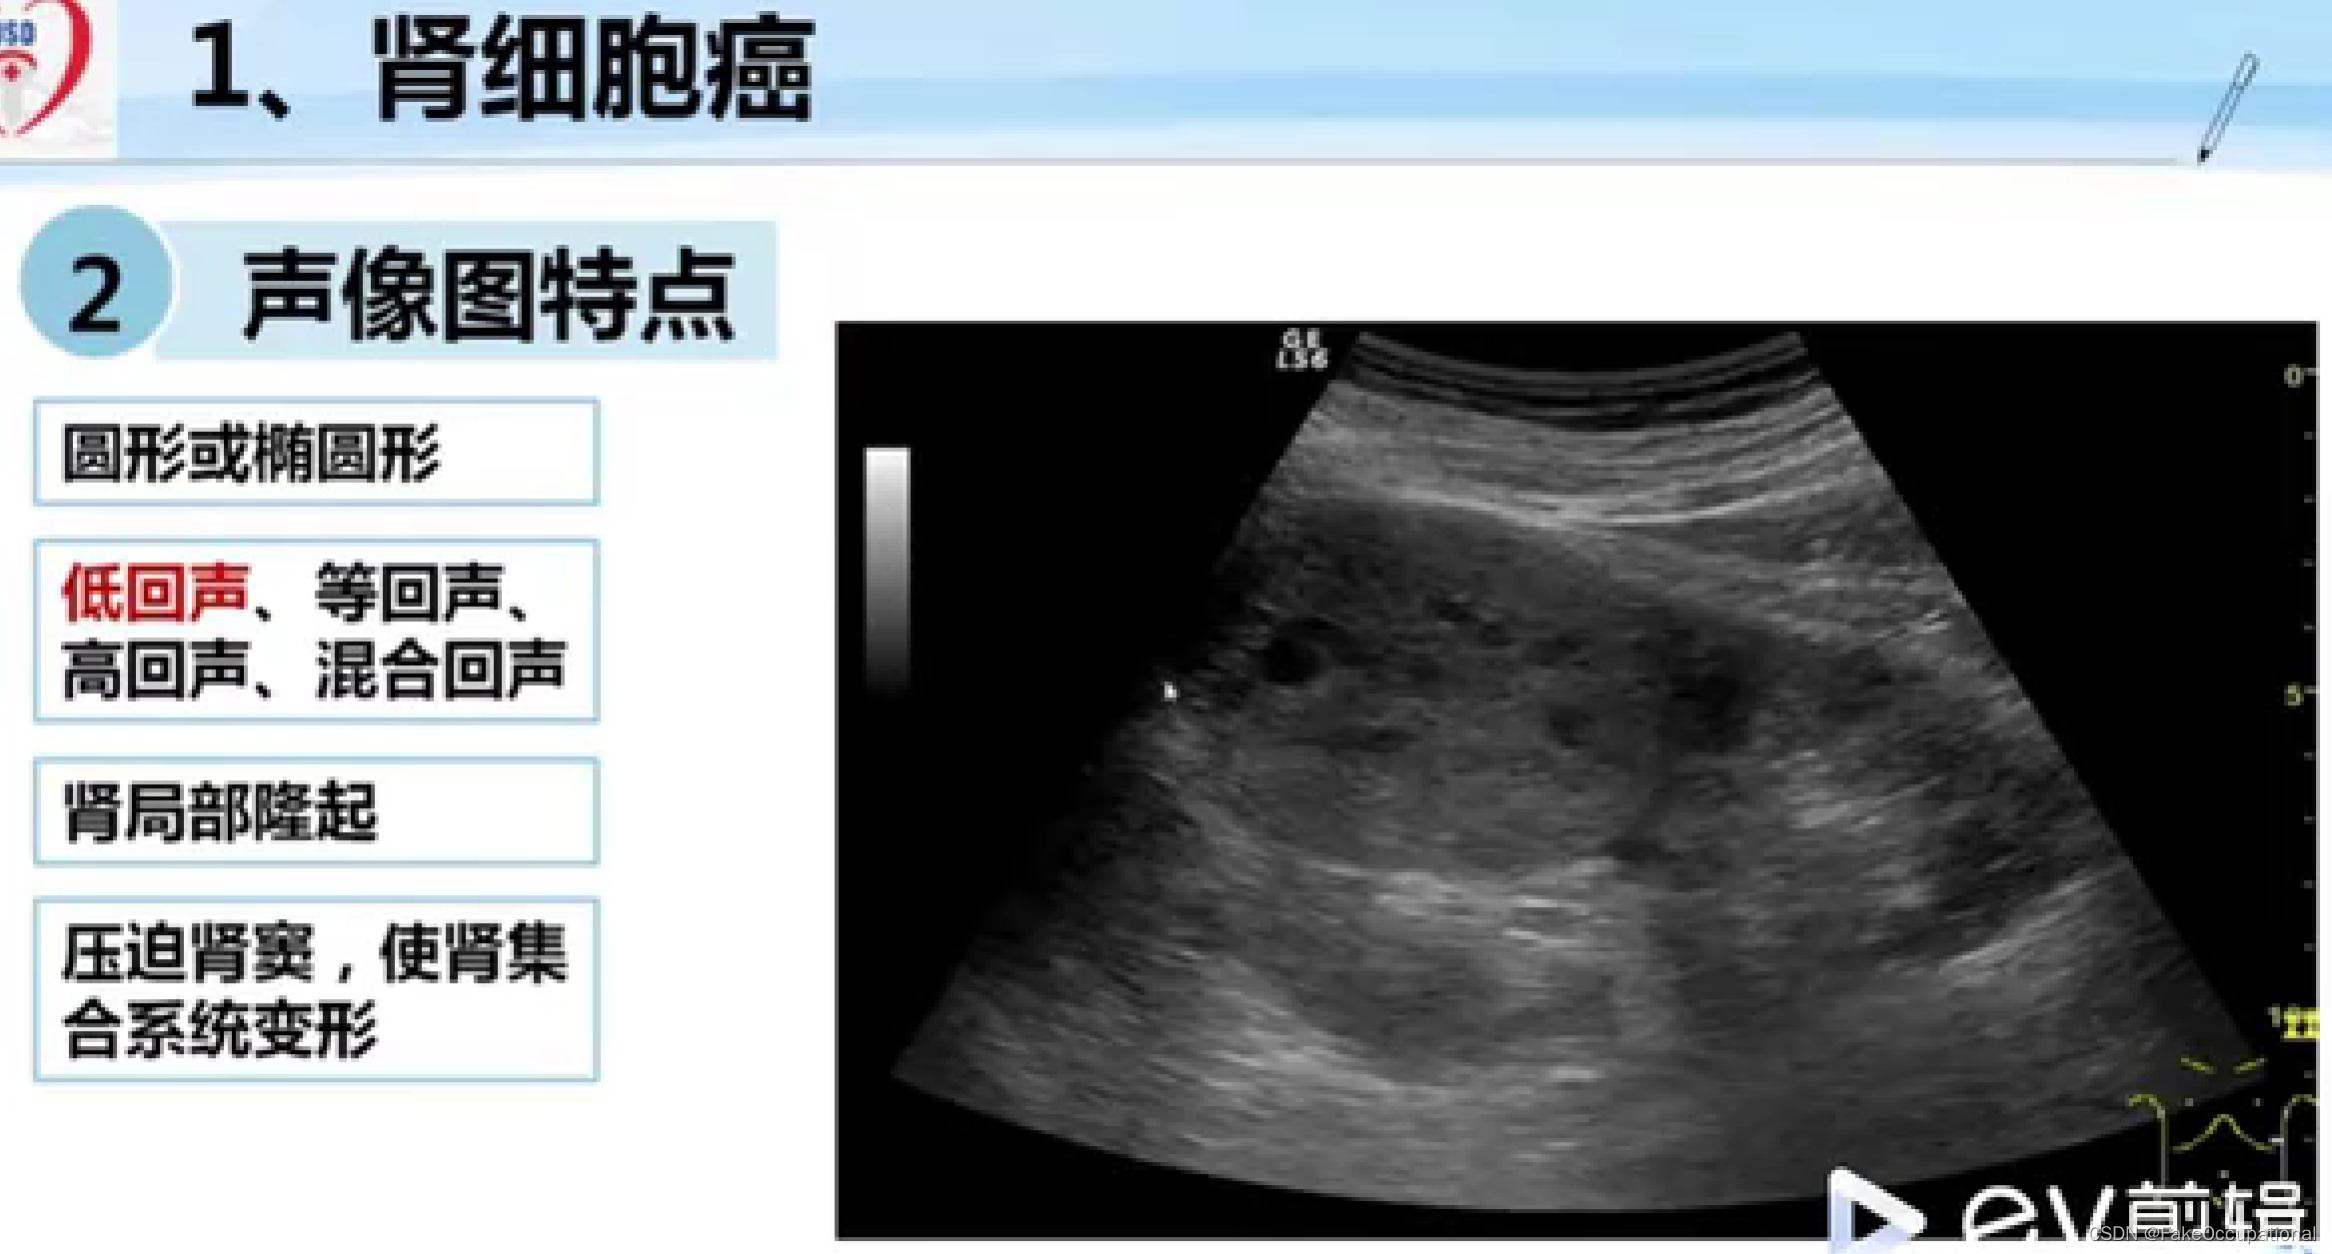

- 掌握肾脏、输尿管膀胱及前列腺疾病的超声诊断要点.1超声表现。熟悉泌尿系统的正常检查技术。了解泌尿系统的超声

- 重点内容:泌尿系的常见疾病

- 难点内容:泌尿系疾病的肿瘤,尤其是恶性肿瘤。